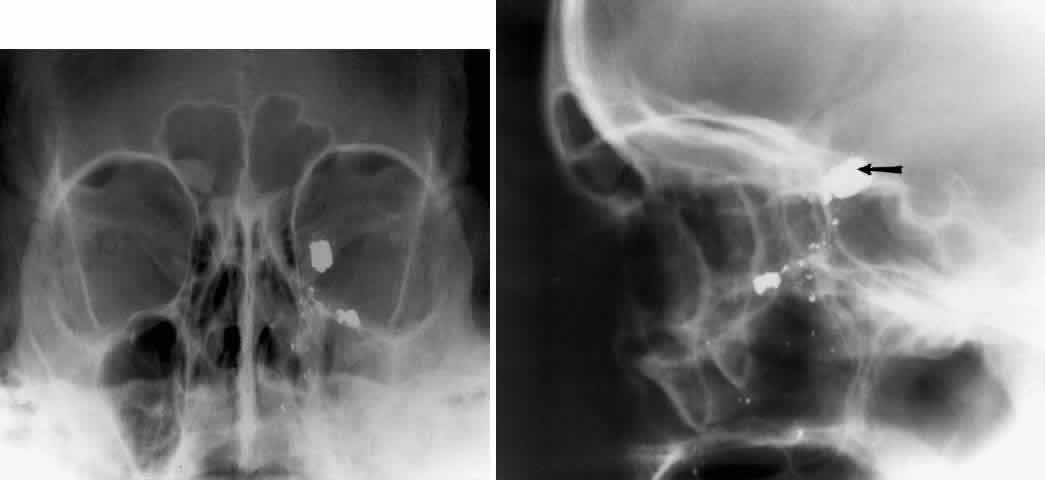

The localization of foreign bodies with plain films is a recurring challenge. Echography and CT have diminished the need for plain film techniques for localization of foreign bodies, but the latter can be used when other imaging modalities are unavailable. Frontal and lateral projections are standard views in these studies (Fig. 18). Localization of a foreign body within the globe is possible with bone-free examination using dental film or by ocular rotation. This latter study localizes the foreign body to either the anterior or posterior segment of the eye. If the foreign body is anterior, the object will rotate in the same direction as the eye. The object will move in an opposite direction to eye movement if its location is in the posterior segment of the eye33 (Fig. 19). Pfeiffer34 and Worst35 used contact lenses as reference devices in localizing foreign bodies. These techniques are less commonly used.

Fig. 18. Foreign body localization using a frontal and lateral projection. A. Caldwell projection of a patient with a gunshot injury to the left orbit. B. Lateral projection with a large metal fragment (arrow) in the orbital apex.

Fig. 19. Foreign body localization using the ocular rotation technique. The patient is directed to look up, as in A, which shows the foreign body moving in the direction of upgaze. B. Foreign body is seen in an inferior location after the patient looked down. This foreign body was located in the anterior segment of the eye.